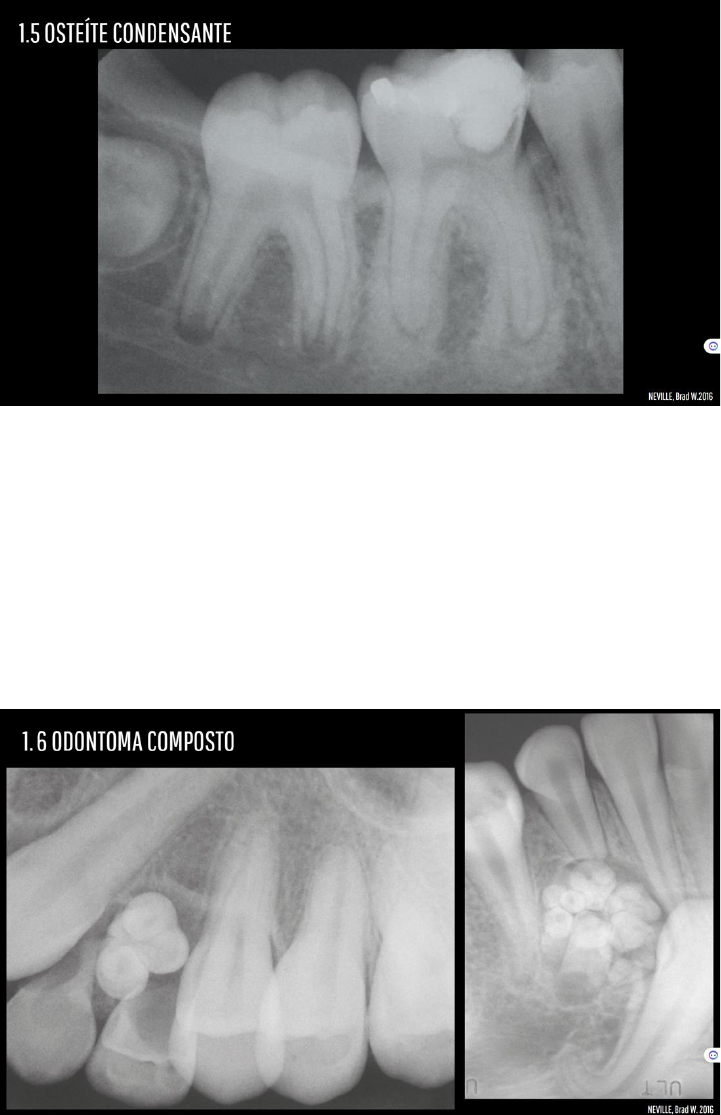

Grátis: Osteíte condensante osteomielite esclerosante focal | Conceito, Características Clínicas, Tratamento e Prognóstico | Patologia Oral - Material Claro e Objetivo em PDF para Estudo Rápido

Grátis: AULA 07 Osteomielite (PARTE II) e lesões potencialmente malignas - Material Claro e Objetivo em PDF para Estudo Rápido